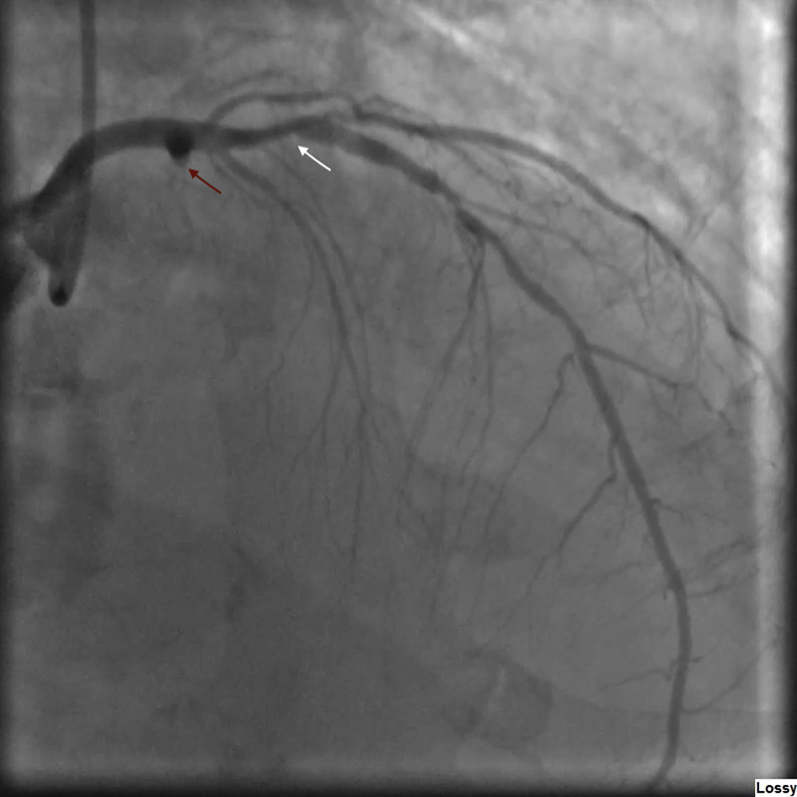

Figure 3.

Right Anterior Oblique Coronary Angiogram

Coronary angiogram right anterior oblique view shows a culprit 100% occlusion of the left circumflex coronary artery (red arrow) and a nonculprit left anterior descending artery with 90% proximal stenosis (white arrow). LAO = left anterior oblique.

Electrocardiography revealed a posterior ST-segment elevation myocardial infarction (STEMI) (Figure 1) for which he received tenecteplase, clopidogrel, and aspirin. He was airlifted to the authors’ hospital for coronary angiography due to ongoing chest pain and persistent ST-segment elevation. Angiography revealed a left-dominant system with a culprit 100% thrombotic occlusion of the left circumflex coronary artery and a nonculprit 90% proximally diseased left anterior descending artery (Figures 2 and 3, Videos 1 and 2). Although the present authors were able to wire past the lesion, balloon angioplasty was unsuccessful due to extensive thrombus burden.